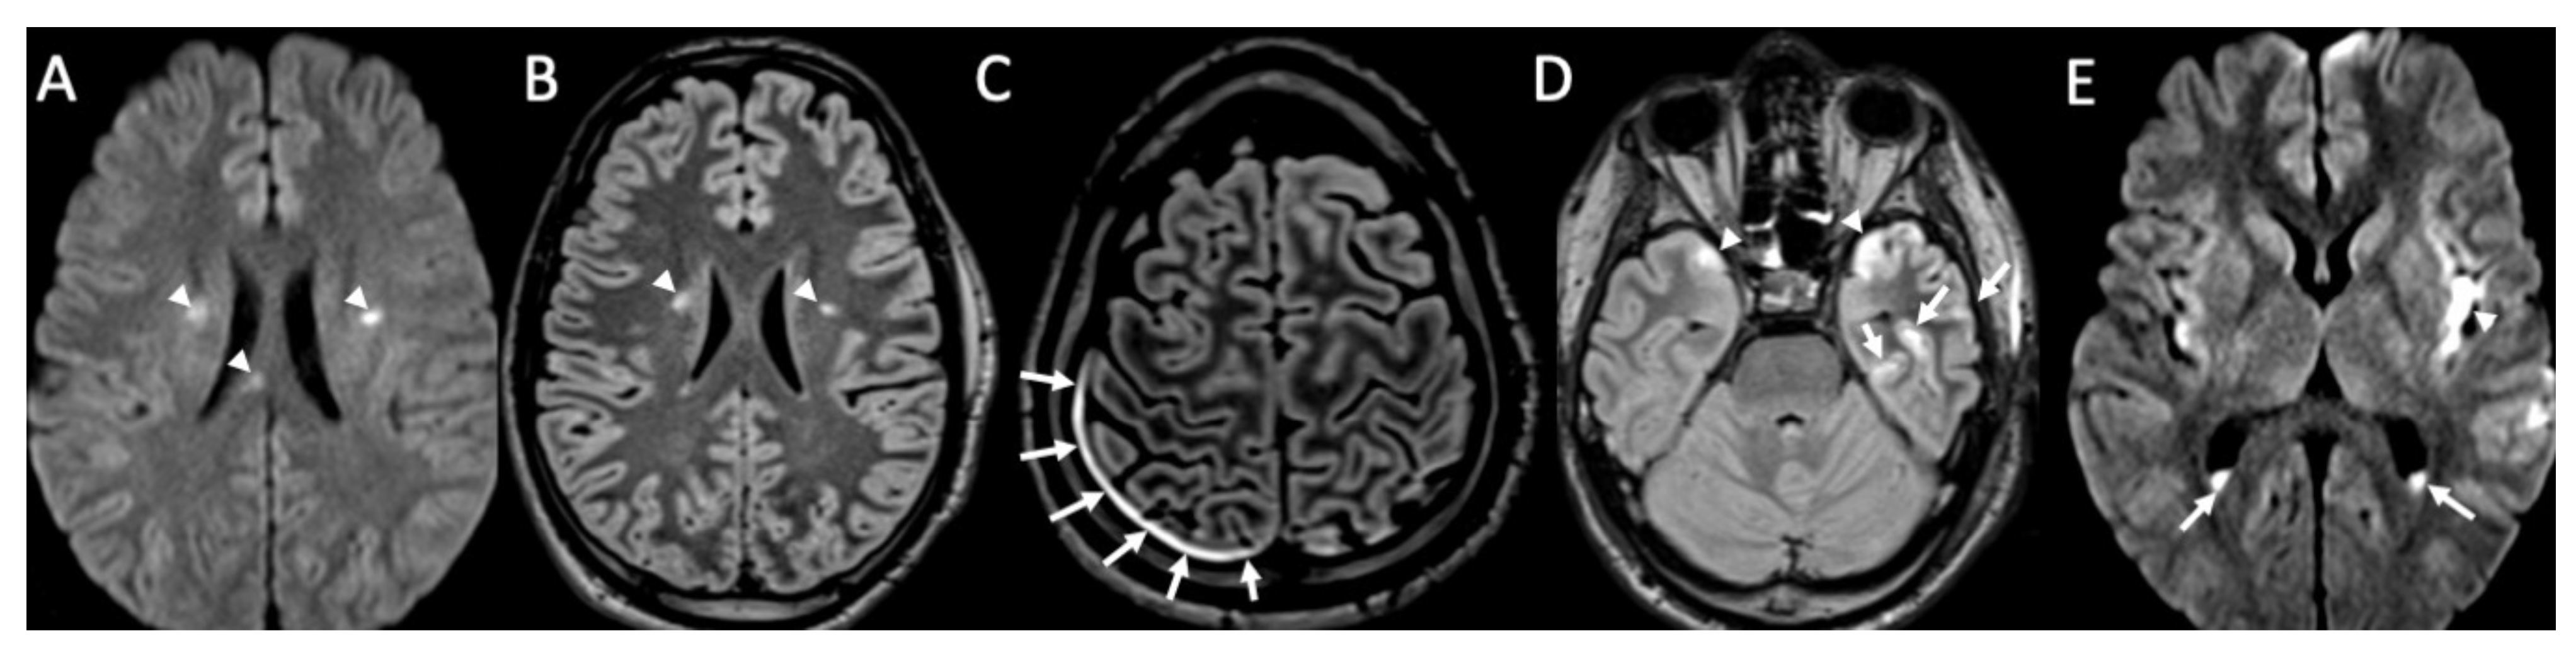

Figure 3.

Axial DWI (A,E), FLAIR (B), enhanced FLAIR (C,D), show multiple recent ischemic areas (arrowheads in A,B,D) in a patient with Neisserria Meningitidis infection. Note also pachymeningeal (arrows in C) and leptomeningeal enhancement (arrows D) and purulent material in the subarachnoid spaces in the left insular region (arrowhead in E) and in the lateral ventricle bilaterally (arrows in E).